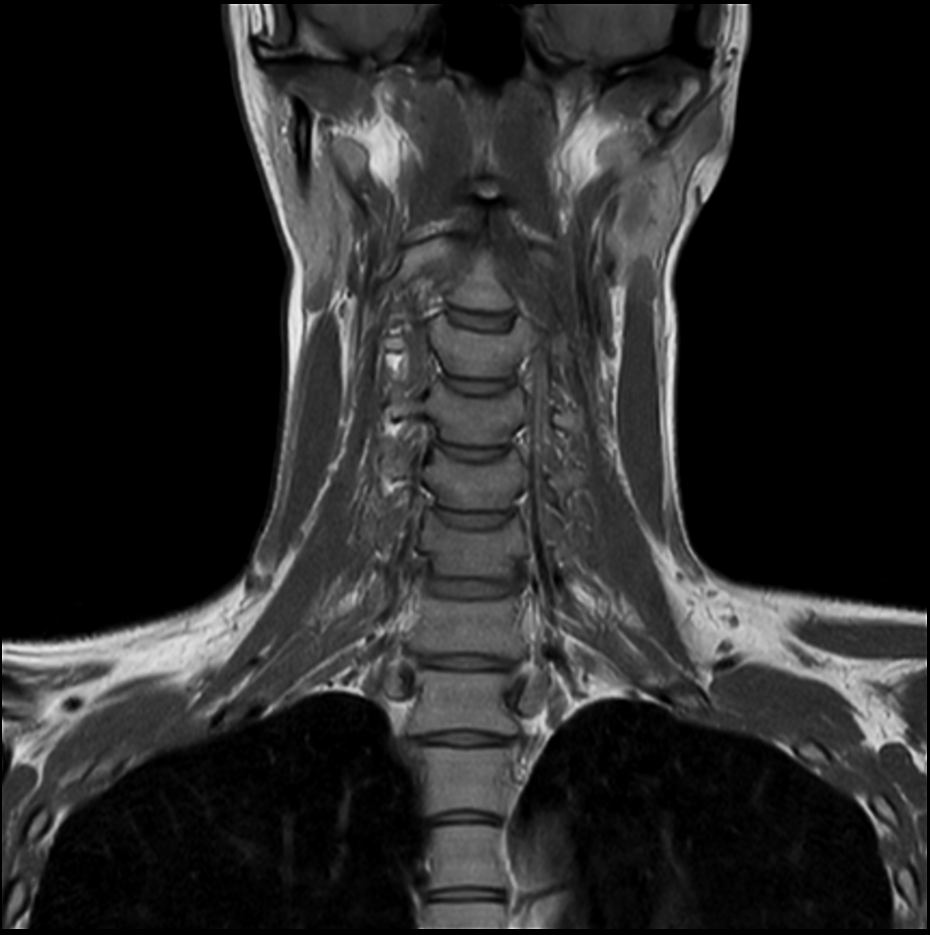

Coronal T2w TSE